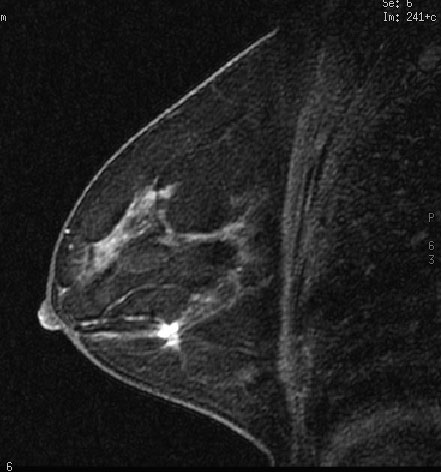

Но, помимо традиционных для МРТ показаний к использованию, метод прочно вошел и в новые для него области. МРТ сердца и сосудов сейчас стала одной из самых динамично развивающихся областей клинического применения метода, крайне интересующей как радиологов, так и кардиологов [1] (Рис.5). МР-маммография (Рис.6), как показали проведенные исследования, может быть высокоинформативным методом исследования молочных желез у определенных категорий женщин с имеющейся или предполагаемой патологией. Оказалось, что МРТ может успешно конкурировать с ПЭТ в выявлении метастатических поражений скелета. Клинический опыт показал, что МРТ существенно лучше, чем КТ при исследованиях внутренних и наружных половых органов у женщин и мужчин, в частности, при выявлении патологии предстательной железы и семенных пузырьков. Появились работы по применению МРТ для изучения паренхимы легких, тонкой и толстой кишки, желудка [10] – тех органов, в отношении которых еще 10-15 лет назад никто не мог предположить, что новый метод диагностики будет использоваться и для этих органов.